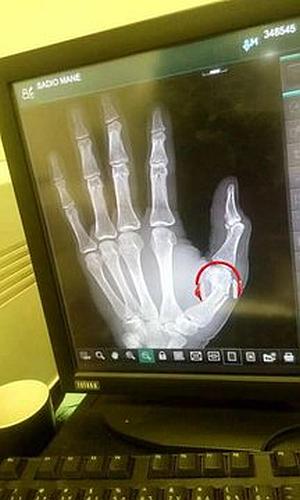

وكان ماني “26 عاما” أجرى فحوصات طبية يوم الاثنين قبل 24 ساعة من موعد مباراة السودان والسنغال التي أقيمت في الخرطوم يوم الثلاثاء ضمن التصفيات المؤهلة إلى أمم إفريقيا، وكسبها منتخب السنغال بهدف دون مقابل، وغاب ماني عن المواجهة لتعرضه للإصابة بكسر في إبهام اليد اليسرى حسبما كشفت الفحوصات الطبية التي نشرتها الصحافة البريطانية، بعدما تحصلت على صور من الفحوصات التي نشرها فني الأشعة.

وعبر الجهاز الإداري للمنتخب السنغالي عن عدم رضاه من نشر الصور الخاصة بفحوصات اللاعب من قبل المستشفى وطالبت البعثة بمحاسبته، وتقرر تحويل فني الأشعة إلى لجنة تحقيق وإيقافه عن العمل وفقا لموقع “النيلين” السوداني.